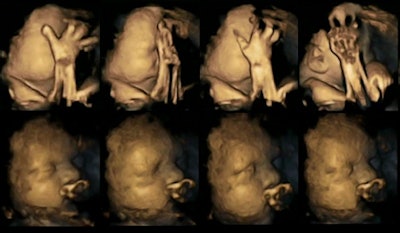

4D ultrasound scans show movement differences in two fetuses at 32 weeks, above and below. The top strip of each image shows movements of a fetus whose mother smoked, while the bottom strip shows a fetus whose mother did not smoke. Images courtesy of Dr. Nadja Reissland, Durham University.Four of the fetuses were carried by women who smoked an average of 14 cigarettes a day. The other 16 fetuses were carried by women who didn't smoke. All fetuses were healthy when born.

The researchers tracked mouth movements on the scans, and they found a statistically significant difference between the fetuses carried by the smoking women versus those of the nonsmokers (p < 0.02). The fetuses of the smoking women showed a higher rate of movements than the normal declining rate expected during pregnancy, and the differences between the smoking and nonsmoking groups widened as the pregnancies progressed.